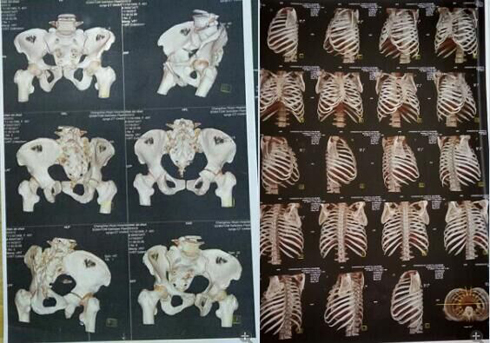

我叫陈新春,女,1968年3月出生,小学文化程度,江苏省盐城市射阳县人。2017年11月3日,在江苏省常州市新北区文化广场工地,八号楼二楼清理施工垃圾。因安全措施不到位,从6米高空施工洞坠入,造成颈椎骨折,脊柱骨折,腰椎L1一6横突骨折,腰椎右侧横突骨折,右侧髋臼,股骨头骨折装钢板,盆骨右侧L1一5骨折,左侧L1一5骨折,双侧耻骨折,左侧髋臼可疑骨折,腰椎至骨盆除左侧髋臼可疑骨折,全部骨折,外阴跌撕,胸椎骨折,内骨粉质性骨折,内骨右侧横突L1一4骨折,内骨左侧3一7两处骨折,右侧肋骨L1一10骨折,右侧肋骨后缘3一7两处骨折,左侧肋骨1.2.3.5.6.7.10骨折,后缘肩往下1一4两处骨折,左肩袖损伤肌健骨折;左冈上肌损伤,左肱骨因血液不流通,左肱骨长一个小圆形囊肿,腹部闭合性损伤,全身多处软组织损伤;双侧微量气胸,肝挫伤出血,脾挫伤出血,左肾挫伤出血,右肾上泉挫伤伴血肿,右肺上叶及两肺下叶挫伤出血,内腹部都挫伤出血。

这里所提供的几张片子拍出的颈椎骨折,腰椎横突骨,脊柱骨折,左侧盆骨骨折,内骨粉质性骨折,内骨左侧3一7两处骨折胸椎骨折,报告单都没有。报告单上有50根骨折包括两处有的,只出三分之一的骨折。常州市武进人民医院涉嫌隐瞒我的伤情,进手术室开刀涉嫌隐瞒了主要骨折的片子,去要片子不给;补出院小结,补两次,颈椎骨折,腰椎骨折,胸椎骨折,内骨粉质性骨折还不肯补。